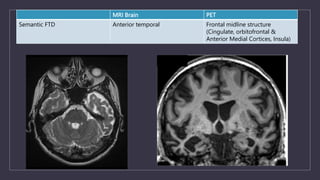

MRI Brain PET

Semantic FTD Anterior temporal Frontal midline structure

(Cingulate, orbitofrontal &

Anterior Medial Cortices, Insula)